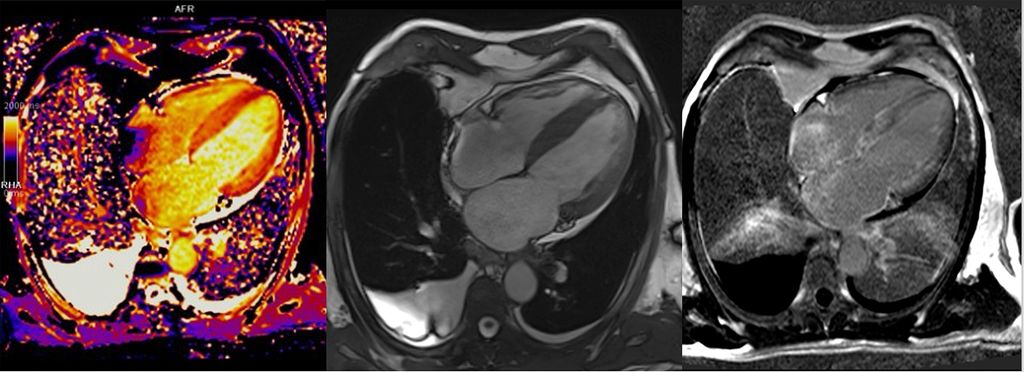

Neben einer reproduzierbareren Beschreibung der kardialen Geometrie sowie einer exakten Messung der kardialen Funktion ist auch eine Gewebebeurteilung mittels T1- und T2-gewichteten Mappings zur differenzialdiagnostischen Beurteilung der zugrunde liegenden Kardiomyopathie möglich. Mit dem „late gadolinium enhancement“ (LGE) können außerdem Fibroseareale dargestellt werden und in die Risikostratifizierung einfließen. Hier konnte gezeigt werden, dass Patient:innen mit HCM/HOCM und >15% Fibrose des LV oder LVEF<50% ein erhöhtes Risiko für maligne Herzrhythmusstörungen bzw. plötzlichen Herztod (SCD) haben, weshalb eine primärprophylaktische Therapie mit ICD unabhängig von anderen klinischen Charakteristika erwogen werden kann.11

Über die Bestimmung des extrazellulären Volumens (ECV) kann außerdem der Verdacht auf eine Speichererkrankung erhärtet werden (Abb.4). Auch seltene Erkrankungen wie M.Fabry haben charakteristische Befundkonstellationen im kardialen MRT (Tab.1).12

Abb. 4:Kardiale MRT bei ATTR-Amyloidose: erhöhtes T1-Mapping (links), 4-Kammer-Bick mit Hypertrophie (Mitte), diffuses subendokardiales LGE (rechts)